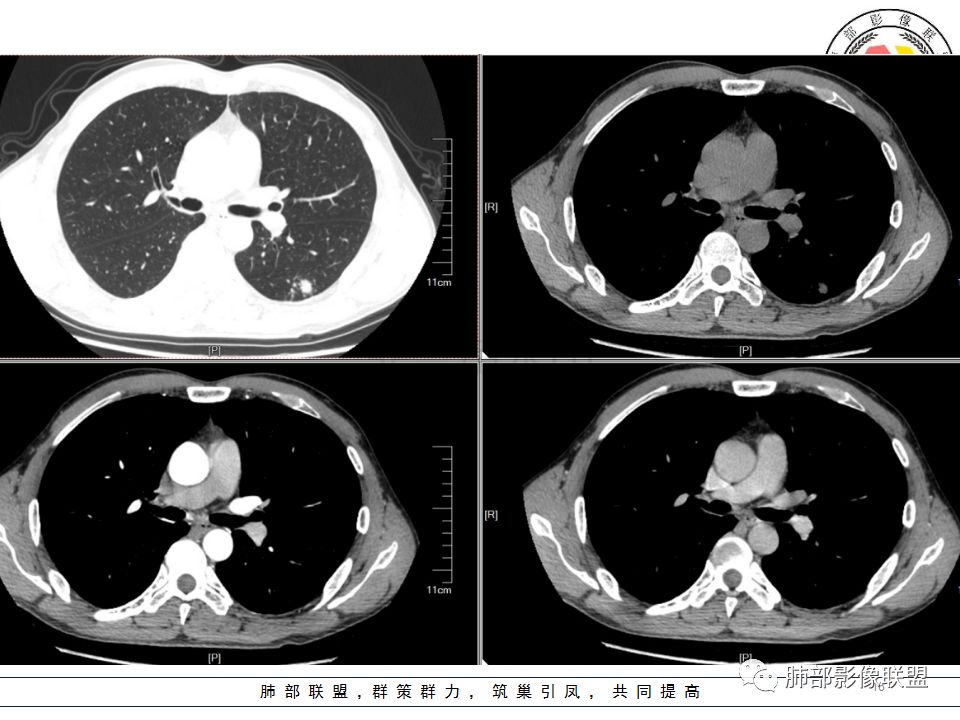

我会做一做支气管的CPR,肺动脉的CPR。

因为南边的考虑一定要看到支气管,怎么办呢?

我很早以前做早癌,就是用CPR技术来观看病灶与支气管、血管的关系。

wonderful:

薄层

岁月:

我的重建图像大部分是这样。

360旋转,可以观看意想不到的效果,我一直很重视这两种重建方法。比想象好 直观。

尘缘:沿支气管由外向内的爬行,常规分析还是考虑结核,小细胞癌待排。

炎症结核这种沿支气管爬的,一般是粘液栓,咳嗽咳痰应该有,很少只是胸痛表现